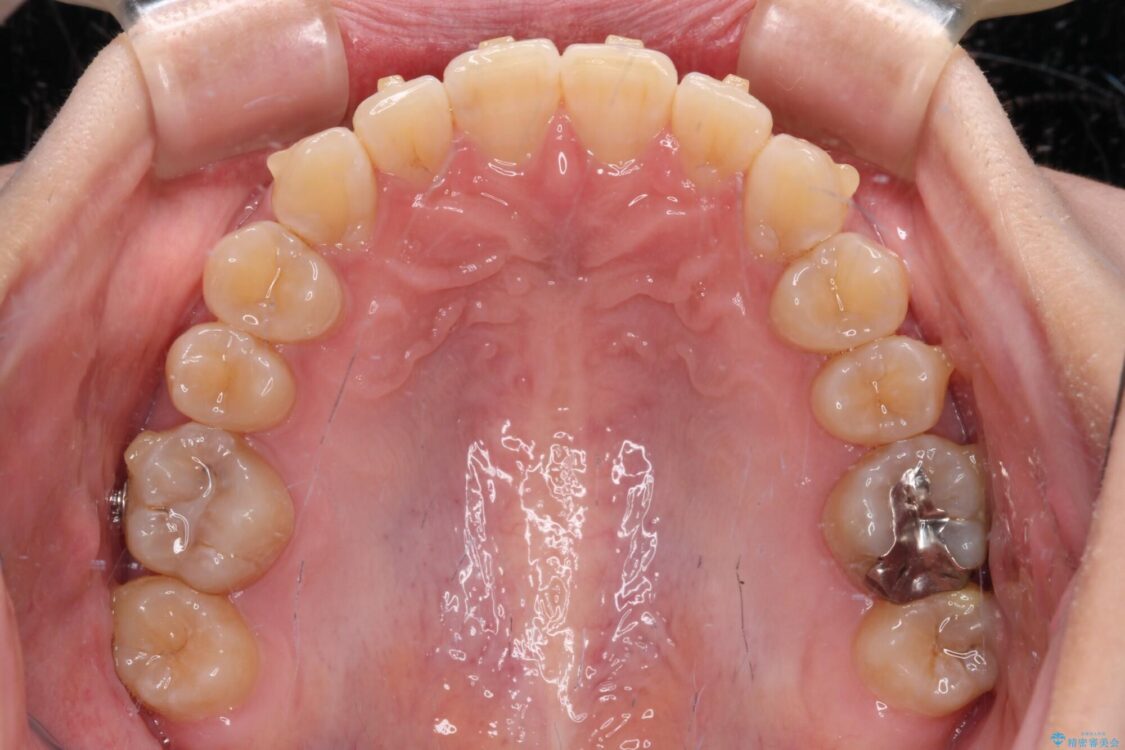

下顎の八重歯を気にして来院された患者様です。

下顎前歯にデコボコが集中していたため、顎間ゴムによる後方移動とIPR(歯と歯の間を削ること)により歯列を整えることとしました。

治療前、下顎前歯のデコボコが集中しており、奥歯の咬み合わせは、上顎に対して下顎が前方位にある状態でした。下顎の歯列を後方へ移動させる治療はインビザラインの得意とするところですので、1年程度で無事に治療を終えることができました。

治療前

• 【モニター】下顎前歯のデコボコをインビザラインできれいに 治療前画像